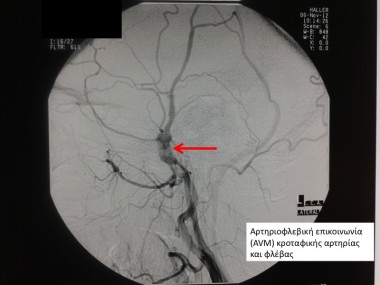

Είναι μια παθολογική μορφή επικοινωνίας αρτηριών με φλέβες, με τη μεσολάβηση δυσπλαστικών αγγείων (πυρήνας/nidus). Η παθολογία αυτή μπορεί να βρεθεί τυχαία (μετά από έλεγχο με MRI ή και CT), μετά από ένα επιληπτικό επεισόδιο ή μετά από αιμορραγία (παρεγχυματικό αιμάτωμα εγκεφάλου).

Αρτηριοφλεβική Επικοινωνία (ΑΦΕ)

Η εν λόγω παθολογία χαρακτηρίζεται από απευθείας επικοινωνία αρτηρίας ή αρτηριών με τις φλέβες. Η ΑΦΕ ή φίστουλα μπορεί να ανευρεθεί είτε τυχαία, είτε μετά από αιμορραγικό επεισόδιο. Στην πρώτη περίπτωση, διενεργούμε μία ψηφιακή αγγειογραφία εγκεφάλου, όπου ταξινομούμε την φίστουλα και εκτιμούμε το αιμορραγικό ρίσκο. Εάν κρίνουμε ότι είναι υψηλό προτείνουμε στον ασθενή επέμβαση με τις ίδιες τεχνικές. Στην περίπτωση της αιμορραγίας, η επέμβαση γίνεται στην οξεία φάση.